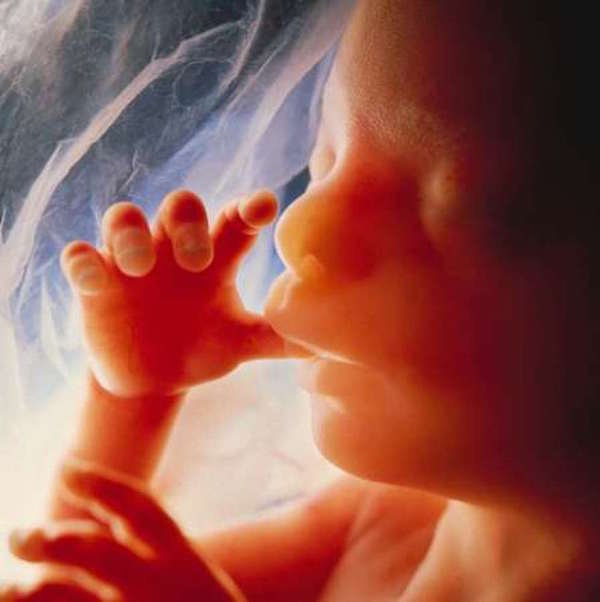

▼她提到自己不反對流產,「畢竟孩子生下來如果不會養,那隻會更慘,但為什麼不早一點呢?」她指出周數大一點的嬰兒往往已經會哭、會動,但許多流掉的嬰兒只能留在盒子裡,痛苦的走…

她深深勸導道:「拜託各位,如果你還沒準備好一切,如果你沒有肩膀負起責任,請你不要懷孕,如果你懷孕了,請你在心跳開始前(6週)到診所、到醫院處理。」她也提到月經遲到的一定要驗孕,不要只是單純覺得太累月經晚來,等發現時可能已經太晚。